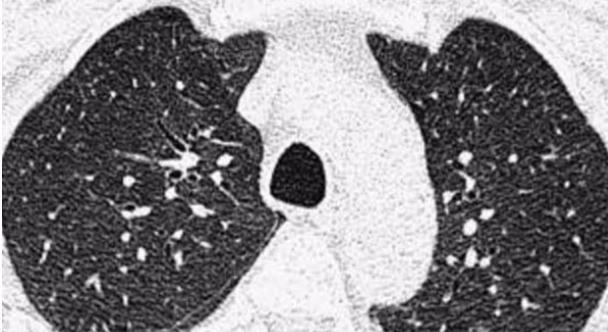

左肺上叶结节

【 结节|如何让你的肺结节变小甚至消失?听听医生怎么说】另外还有一部分结节患者,他们的炎症是近期的甚至正在经历着炎症,这一部分人炎症消失之后,肺结节是有可能变小甚至消失的,这也是为什么有一部分结节患者当查出结节之后,医生告诉你:“去抗炎治疗10-14天左右,再去复查”,这一部分人去复查的时候在炎症消失后发现自己的结节的确变小甚至消失了。